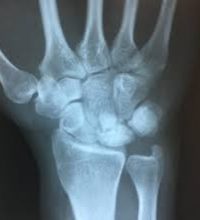

Η διάγνωση επιβεβαιώνεται με ακτινολογικό έλεγχο, αξονική και μαγνητική τομογραφία.